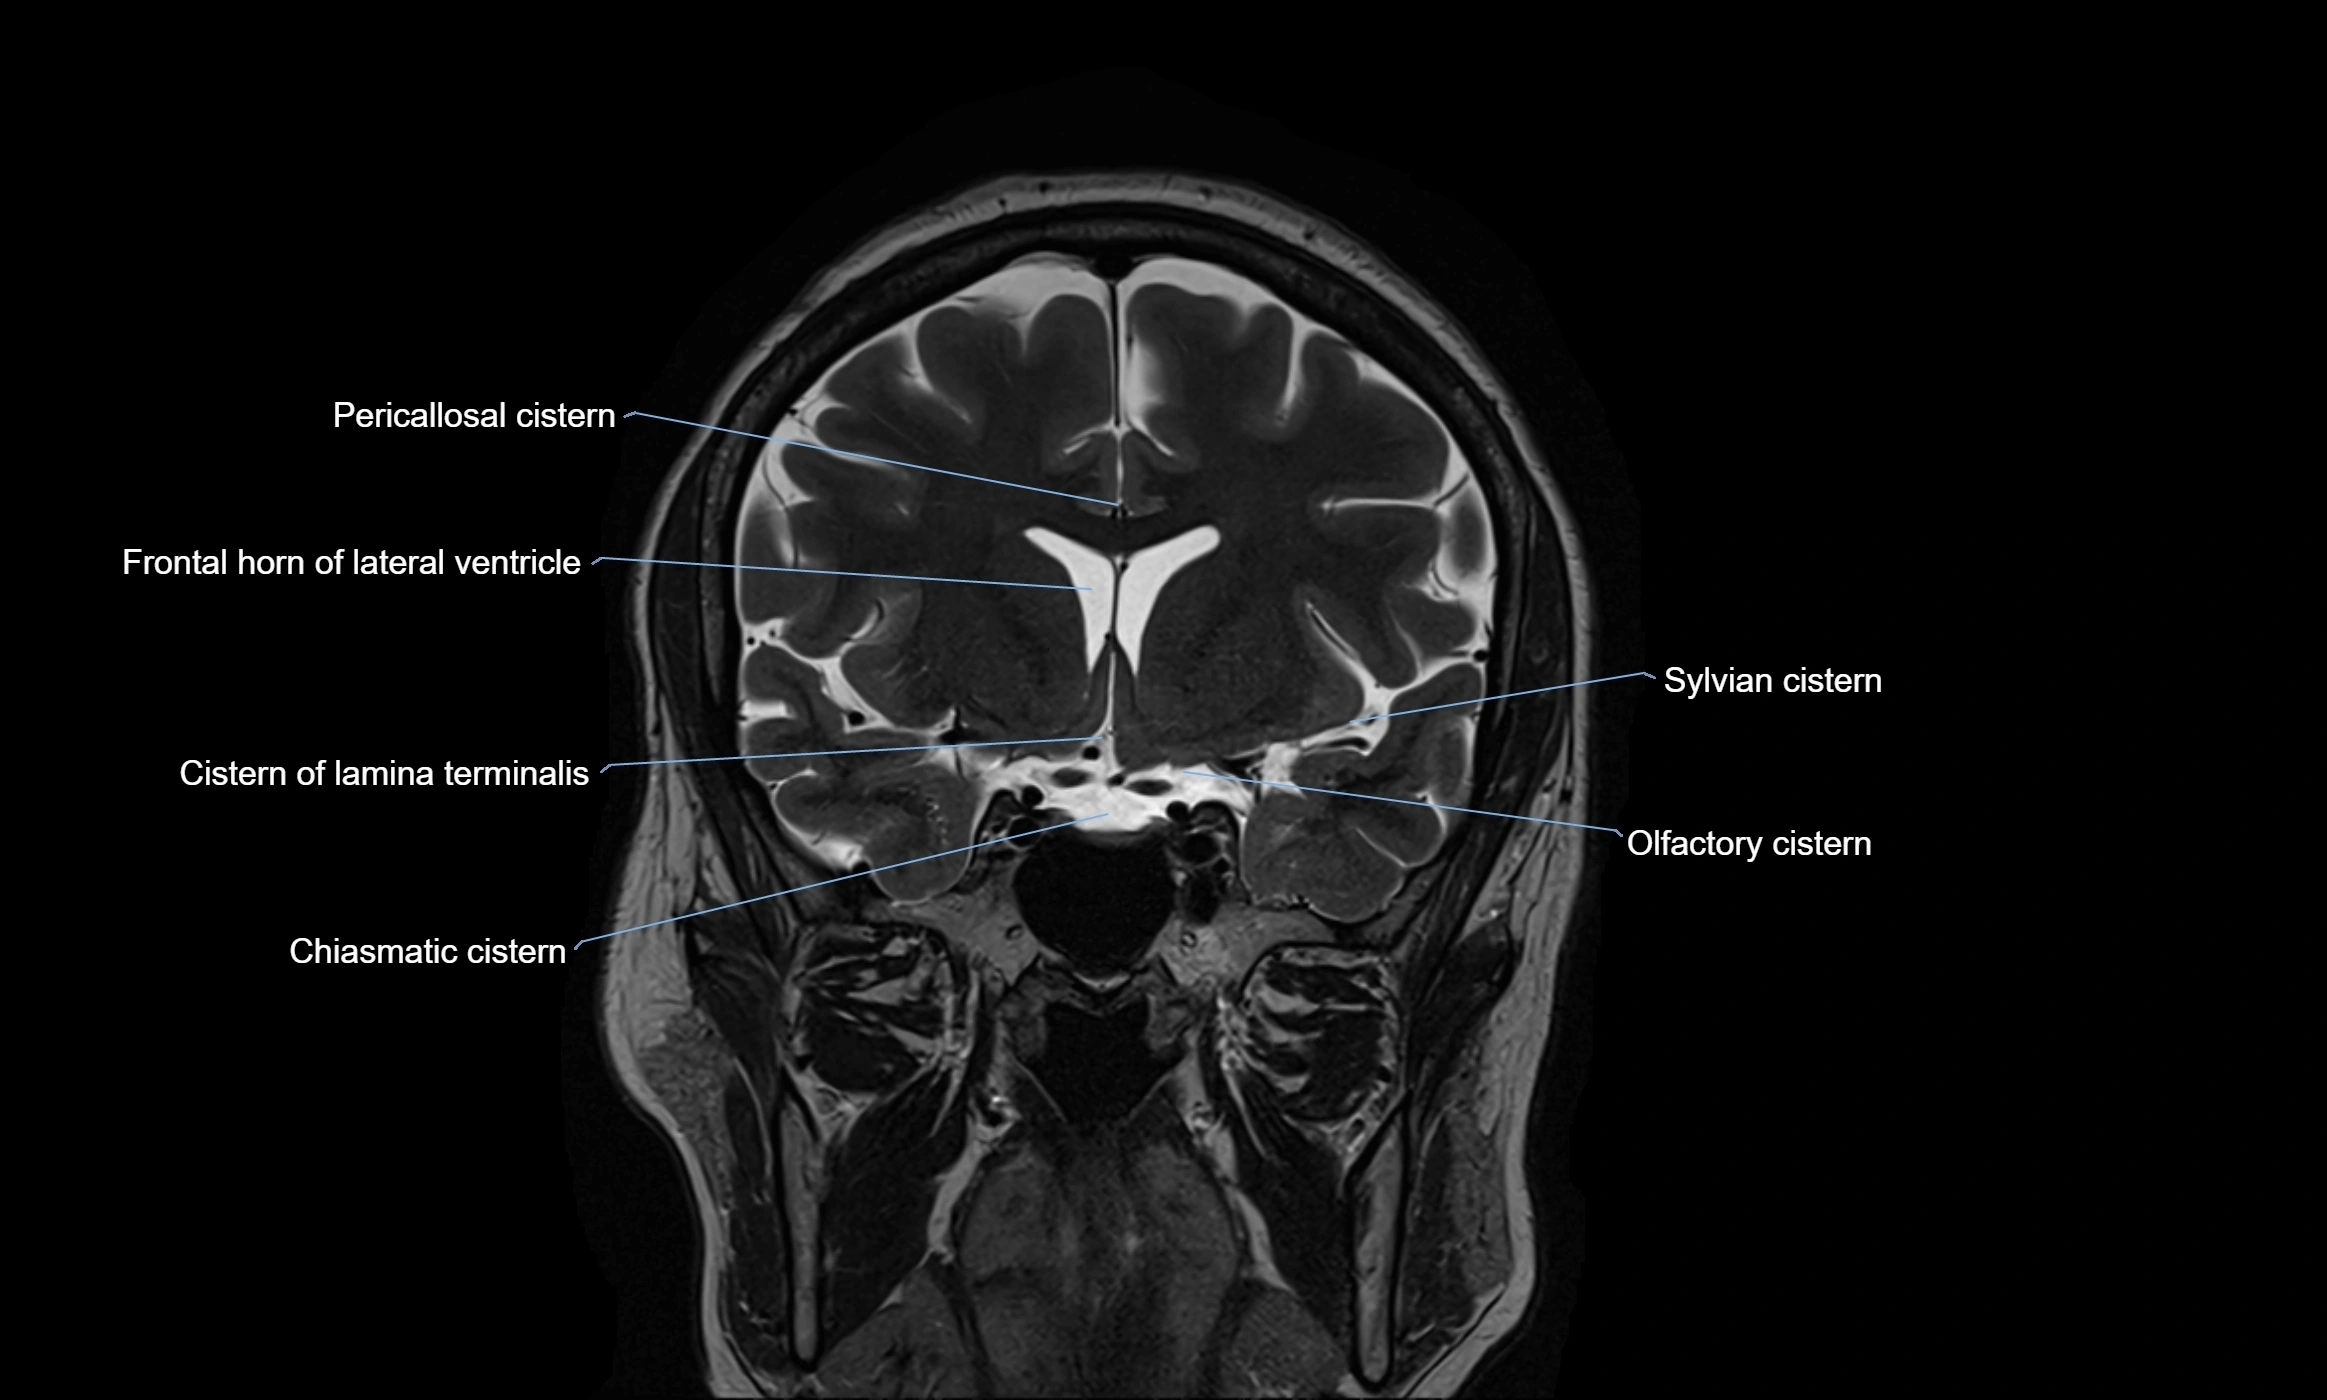

MRI images

image